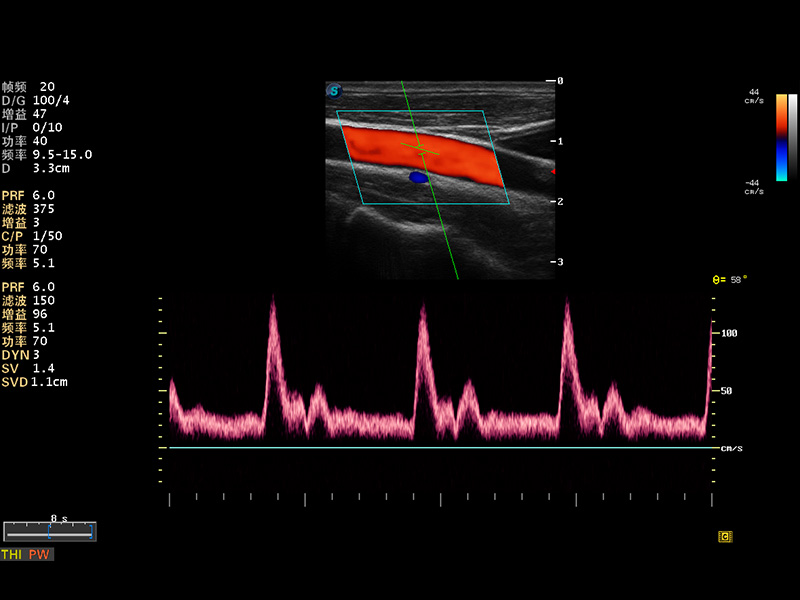

S8 EXP便携式彩色多普勒超声诊断仪是狗万官方网站研发的高端全身应用型便携彩超。高通道的VIS平台融合可视化(Visual)、智能化(Intelligent)和人性化(Smart)的特点,配以狗万官方网站自主研发生产的探头大家族,使您能够快速、准确的获得病人信息,提高工作效率的同时减轻疲劳。